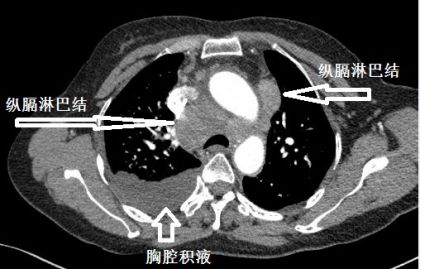

下面这个患者,纵膈淋巴结肿大、融合,心包积液,胸腔积液,一看就是晚期肺癌。后来,纤支镜也确实查到癌细胞。

这个胸水,不好抽,但也不难抽。癌性胸水,不抗癌治疗,不引流,一般不会自行吸收。我带同学去抽胸水,为了安全起见,我事先还是用B超探查了一下胸水,我瞬间就懵了:居然只有极少量的胸水。

复查CT,“癌性胸水”果然无缘无故减少了。

肺癌合并单侧胸水,甚至晚期肺癌合并单侧胸水,不一定是癌性胸水!

这个患者的胸水,应该是心包积液导致静脉回流受阻,体循环淤血引起的。利尿治疗后,胸水减少。

就算是可疑癌性胸水,也要谨慎,之前的影像学检查,要慎重对待!一不小心,就干抽了。